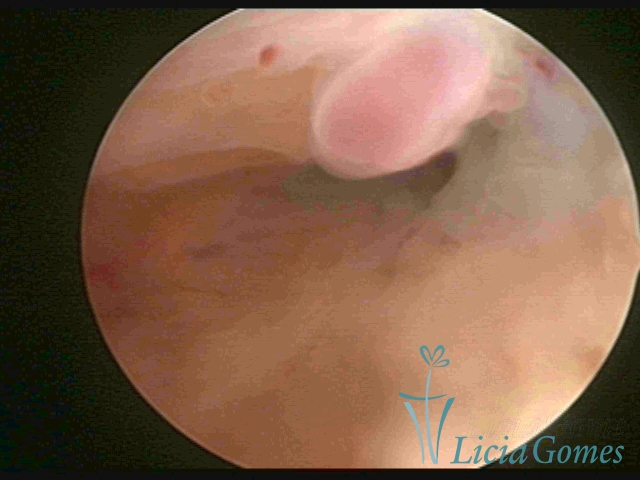

ENDOCERVICAL POLYPS

Benign tumors resulting from the reactive focal proliferation to inflammatory processes or hyperestrogenism situations, which may be sessile (with a large implantation) or stalked.